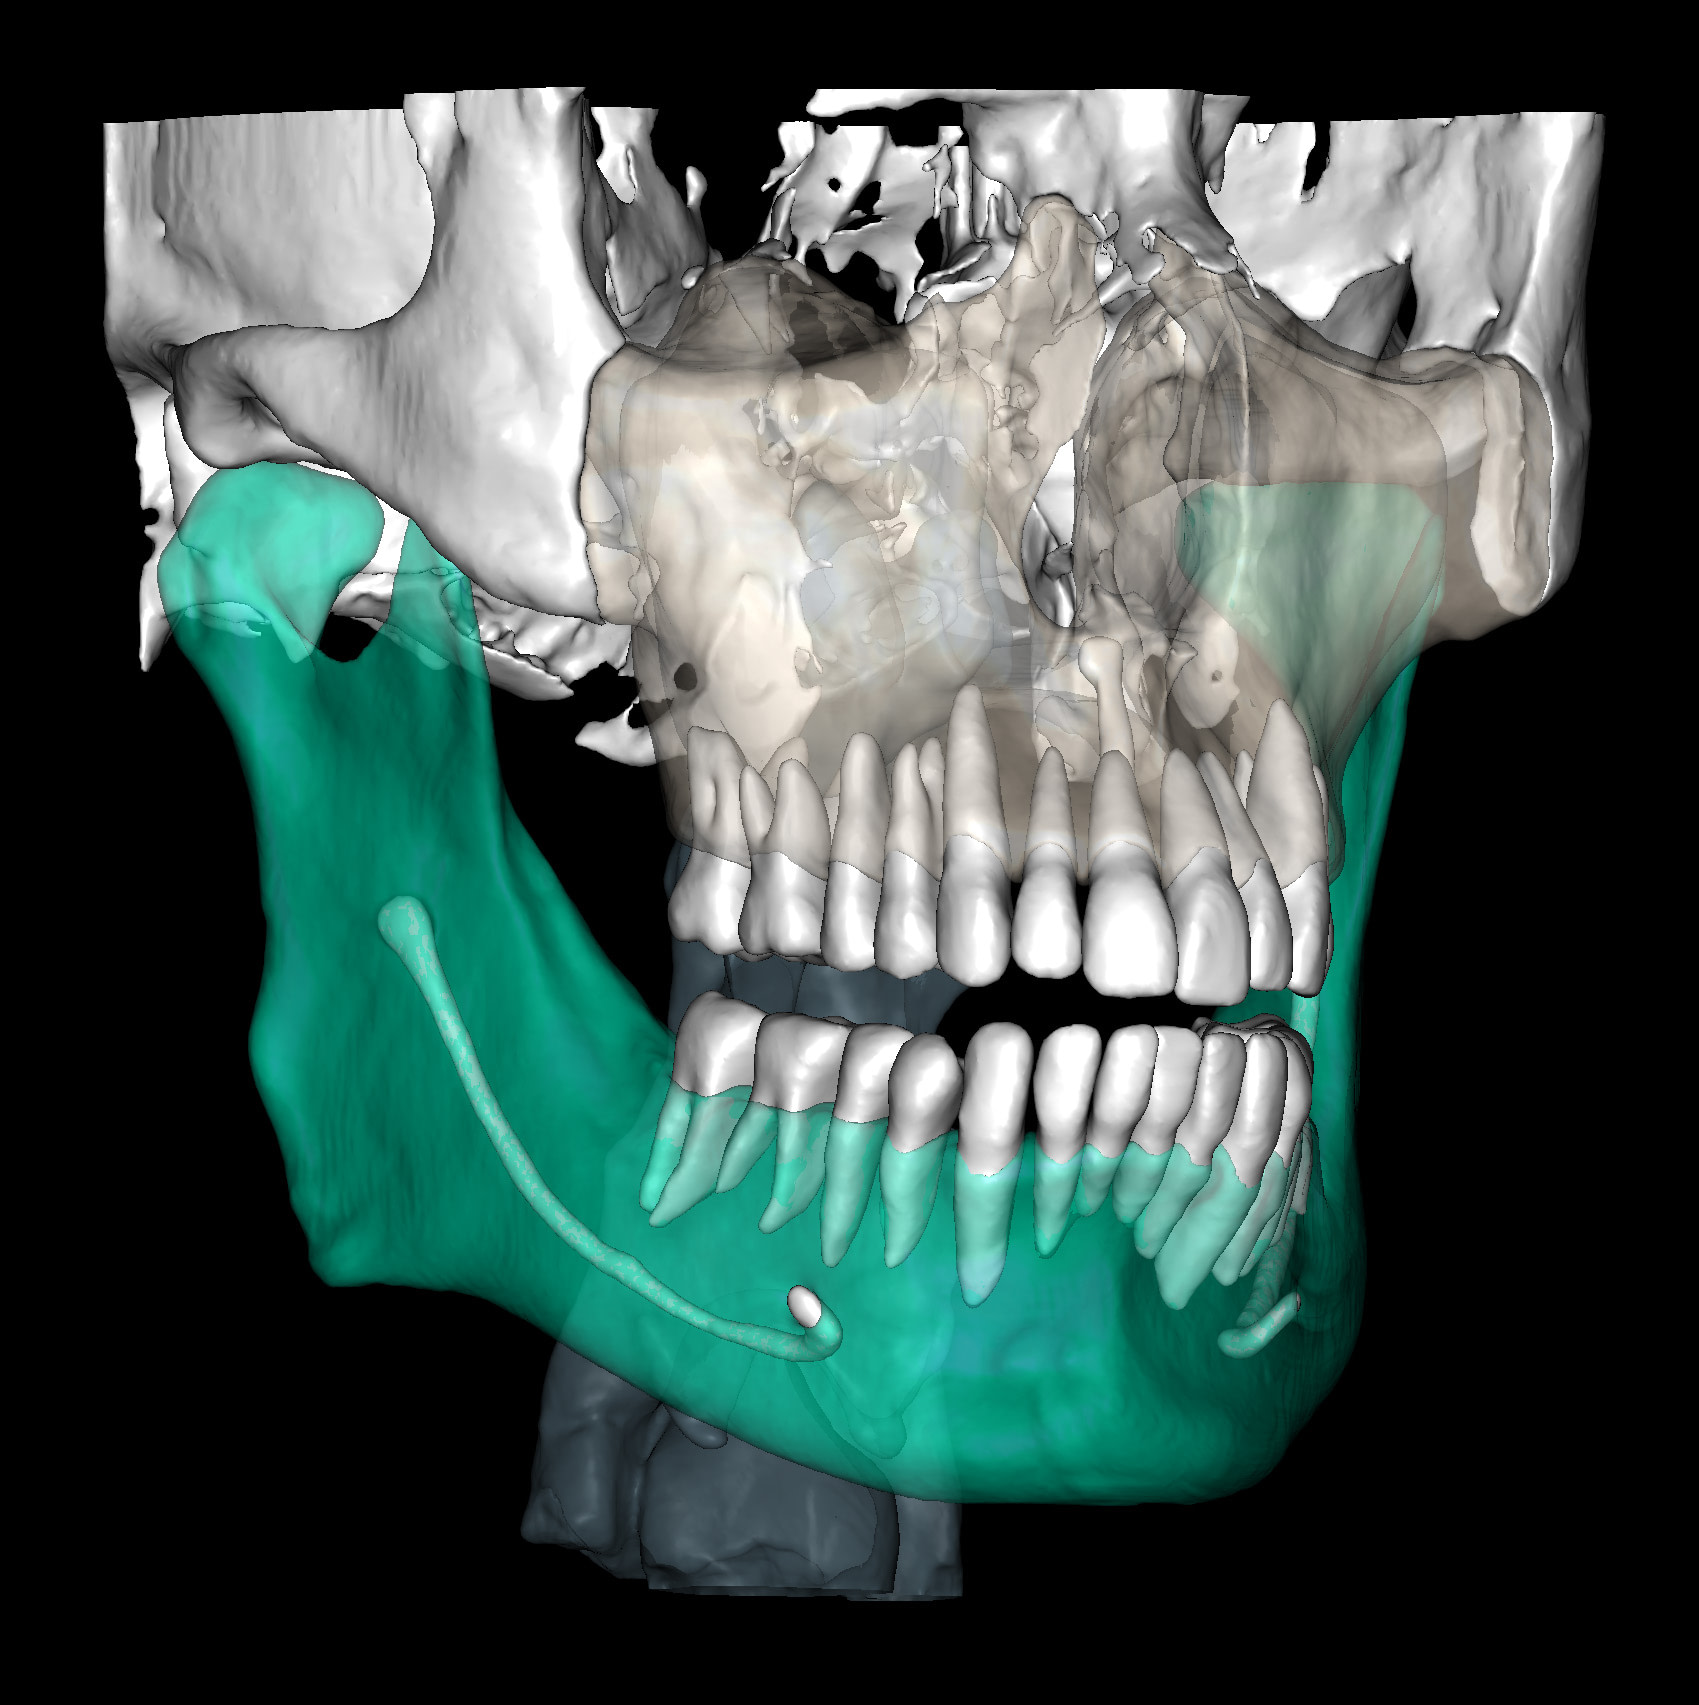

This is one feature that actually made Diagnocat very popular early on. It was the only software that made CBCT segmentation easy. Nowadays, there are several different companies and software that carry out segmentation. Diagnocat was the first and is still arguably the best at it.

So what is Segmentation? It basically means taking the CBCT and delineating all the different 3D structures, bones, individual teeth, etc.

These can then be individually exported via the software by generating STL files from CBCT dicom data. This can be used in other dental software. Jaw STLs can be used in Modjaw (jaw motion capture) for TMJ analysis, for example. As well as in exocad to help visualize the jaws for surgical planning or guide creation.

Being able to take a DICOM file and turn it into STLs is useful for a host of different CAD/CAM indications.

CBCT Segmentation into STL

Generate STL files from CBCT DICOM data.

Generate maxilla and mandible in one STL file or face, teeth, maxilla, mandible, airway, cranial base, canals as separate STL files.